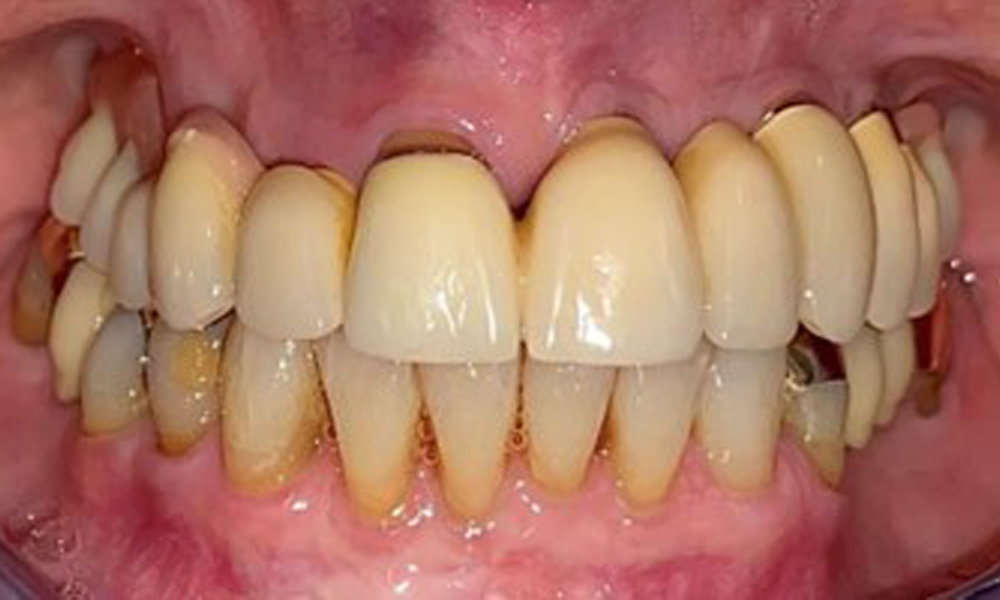

Die Patientin wurde vor über 25 Jahren mit einer kombinierten herausnehmbare Implantat-Teleskopprothese im Oberkiefer versorgt (Abb. 1, Abb. 2, Abb. 3) und ist sehr glücklich über ihren Zahnersatz. Im Unterkiefer hat die Patientin einen suffizienten festsitzenden Zahnersatz. (Abb. 4)

Frontalansicht mit dem eingesetzten Zahnersatz im Oberkiefer.

Abb. 1: Frontalansicht mit dem eingesetzten Zahnersatz im Oberkiefer.

Dentaler Befund

Der dentale Befund stellt sich wie folgt dar: Kombinierte herausnehmbare Implantat- und zahngetragene Teleskoparbeit auf Implantaten 15, 13, 21, 23, 24, 25 und Zahn 11 (Abb. 1, Abb. 2, Abb. 3). Im Unterkiefer ist die Patientin mit einem festsitzenden Zahnersatz versorgt. 37–34 sowie 45–47 haben suffiziente Brücken (Abb. 4). Kronenränder sind intakt, aktive kariöse Läsionen sind nicht vorhanden. An Zahn 43 zeigt sich eine Compositefüllung mit Randspalt. Im Unterkiefer liegen Rezessionen mit freiliegender Wurzeloberfläche zwischen 1 – 3 mm vor. Dies trifft auch für 11 zu.